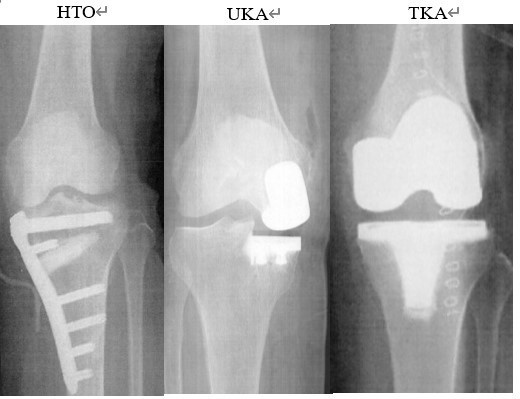

• 当院での膝痛に対する治療

人工関節外科

当院での膝痛に対する治療